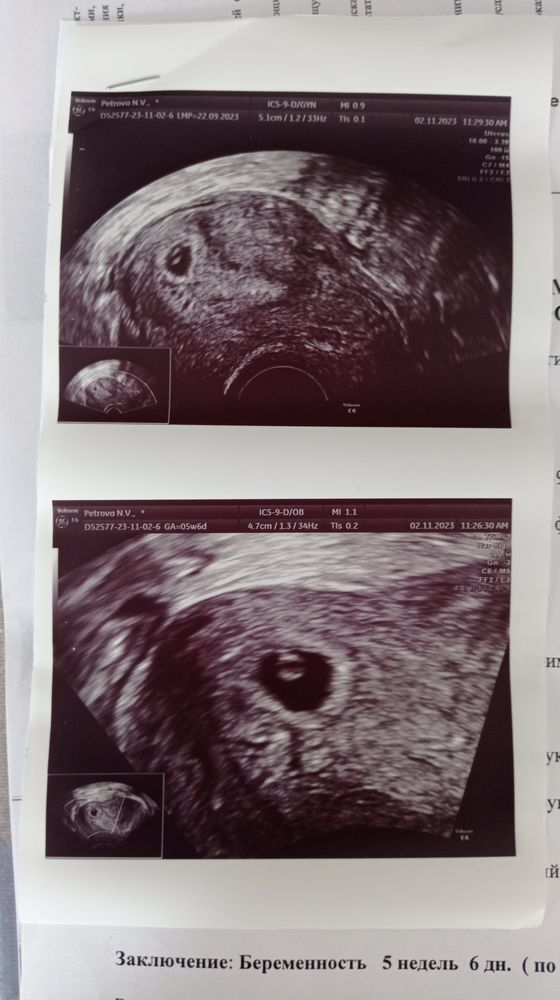

УЗИ 5 неделя

Ниже писала что след УЗИ буду делать 8 числа, но Не удержалась и сходила на УЗИ, в клинику при жк 22 . Так сказать с пользой и на разведку.

Изображение

Для начала море п

В субботу была на УЗИ платно

Всё хорошо, рановато пришла конечно, зато спокойно задала всё интересующие вопросы, услышала благоприятные прогнозы, назначили повторное УЗИ на 8 число. Со слов гинеколога там уже всё будет 😍

Прикрепляю УЗИ